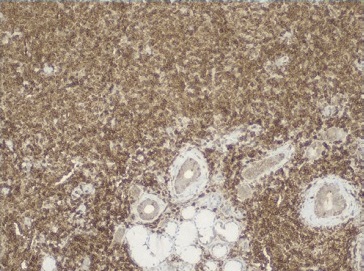

As hipóteses colocadas para diagnóstico diferencial desta lesão apresentadas foram tumores de células salivares (adenoma pleomórfico, carcinoma muco‑epidermoide e adenocarcinoma polimórfico de baixo grau), abcesso de origem dentária/endôntica ou de origem periodontal, e neoplasia linfoproliferativa. Deste modo, procedeu‑se à biópsia incisional que revelou, a nível submucoso, a existência de glândulas mucosas rodeadas por denso infiltrado de células linfoides com vago padrão nodular, assim como espessamento hialino acentuado periductal (Figura 4). Os linfócitos apresentavam tamanho pequeno a intermédio com núcleos hipercromáticos e irregulares, sem lesões linfoepiteliais. A análise imunohistoquímica, revelou expressão de CD20 generalizada com CD10 positivo em áreas nodulares, assim como BCL‑2 e BCL‑6 (Figuras 5, 6 e 7). Estas alterações eram compatíveis com linfoma B folicular, com envolvimento de glândulas salivares minor.

Figura 4 Anatomia patológica da biópsia incisional, revelando existência de glândulas mucosas rodeadas por denso infiltrado de células linfoides com vago padrão nodular